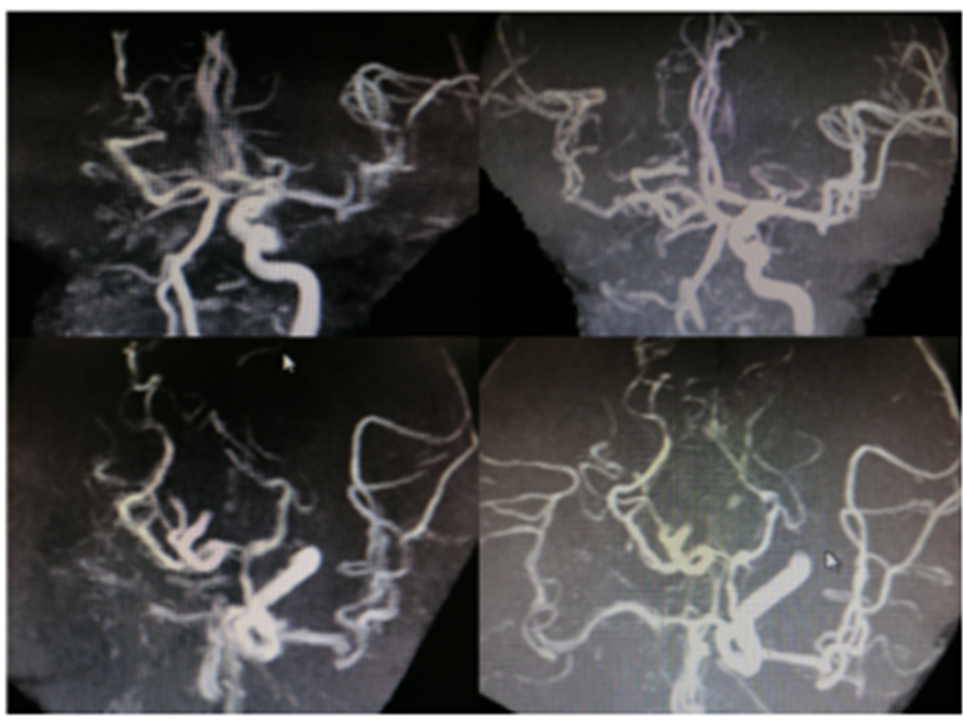

病历夹什么径技·第151期|串联营病历夹:京广连营_https://www.jmylbn.com_新闻资讯_第72张

病历夹什么径技·第151期|串联营病历夹:京广连营_https://www.jmylbn.com_新闻资讯_第73张

病历夹什么径技·第151期|串联营病历夹:京广连营_https://www.jmylbn.com_新闻资讯_第74张

<<滑动查看下一张图片>>

结论:颅脑CT提示左侧基底节、放射冠区腔隙样软化灶。颅脑DWI提示双侧小脑、桥脑、中脑、双侧海马、双侧枕叶、右侧丘脑及右侧胼胝体多发急性脑梗塞。颅脑MRA提示基底动脉及双侧大脑后动脉未见显示;右侧大脑中动脉中-重度狭窄;脑动脉硬化。初步诊断为急性后循环脑梗死,基底动脉闭塞。